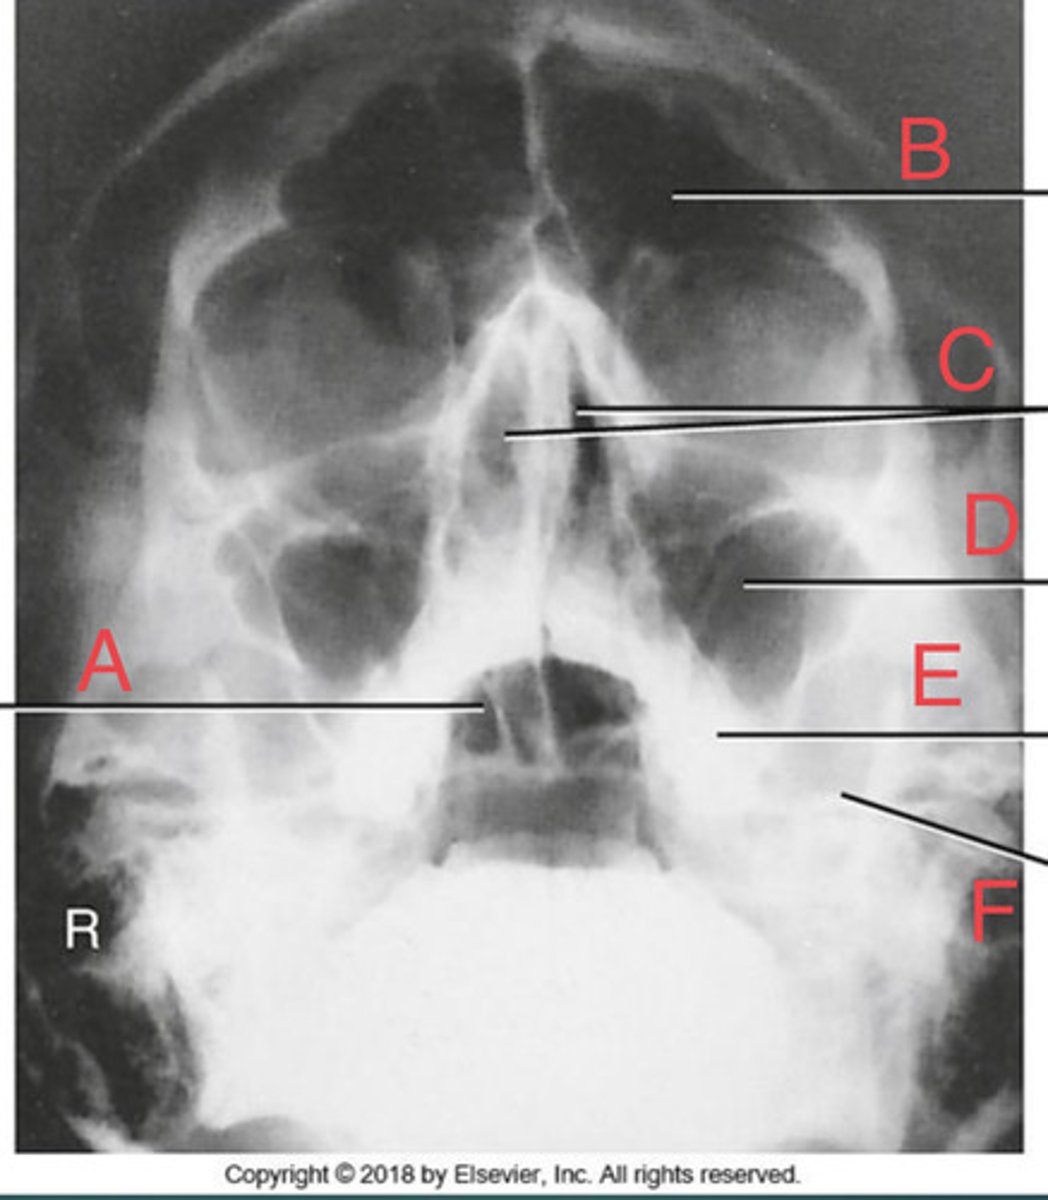

Open Mouth Waters Sinuses

What projection?

R Sphenoid sinus of sphenoid bone

A.

L frontal sinus of frontal bone

B.

Nasal fossa

C.

L. Maxillary sinus Of maxilla

D.

L. alveolar process of mandible

E.

L petrous ridge of temporal bone

F.

L petrous ridge of temporal bone

I.